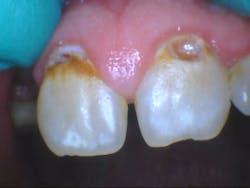

- Additional caries were noted on nos. 10, 11, 14, 26, 27, and 29—primarily facial/buccal caries (figures 3–8)